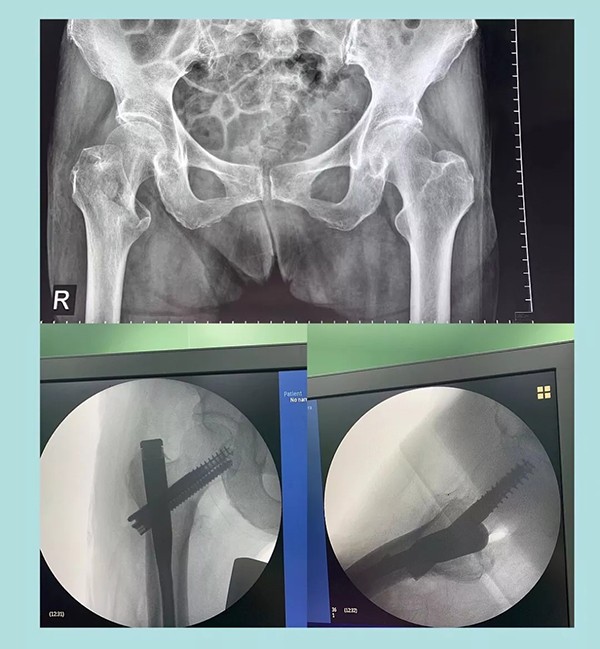

幾天前,蒲奶奶不小心摔了一跤倒地不起,到家附近醫(yī)院檢查后被診斷為右側(cè)股骨粗隆粉碎性骨折。醫(yī)生告知家屬,這種骨折對于老人來說非常棘手,建議保守治療。為提高老人生活質(zhì)量,家人商量后決定放手一搏,在打聽到我院關(guān)節(jié)科對這種病例治療效果非常理想后,立即轉(zhuǎn)往我院。

經(jīng)過內(nèi)科疾病的治療調(diào)理,總體符合手術(shù)條件后,羅軍主任帶領(lǐng)手術(shù)團(tuán)隊為老人實(shí)施了閉合復(fù)位Intertan髓內(nèi)釘微創(chuàng)手術(shù)。為避免全麻對肺功能的影響,術(shù)中沒有使用常規(guī)的全麻氣管插管,而是采取神經(jīng)阻滯麻醉。術(shù)前老人嚴(yán)重貧血,為盡可能減少術(shù)中出血,手術(shù)采用微創(chuàng),且在半個小時內(nèi)順利完成。術(shù)后老人沒有明顯疼痛,術(shù)后一周即下地行走。